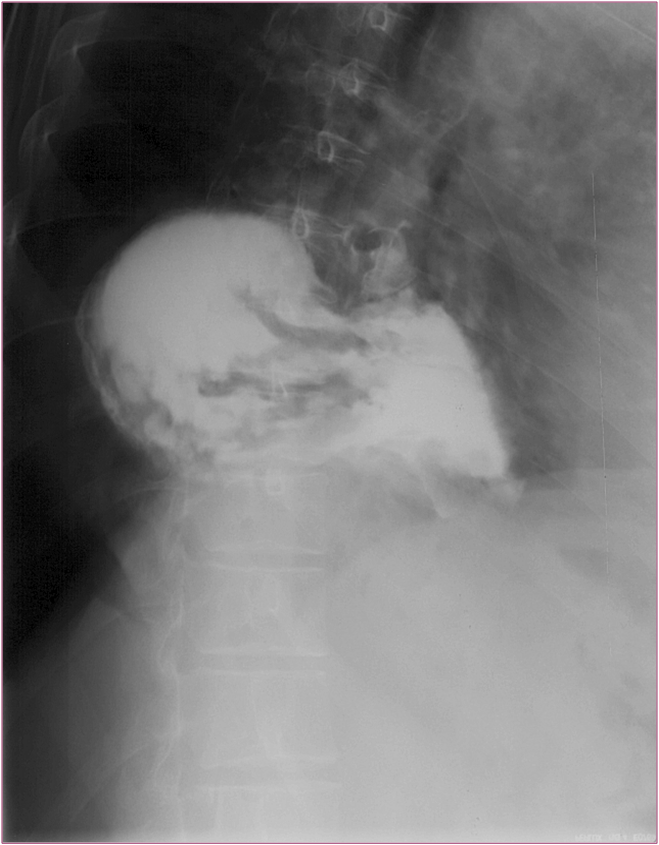

Image Image

Fig.8., 9.:Incarcerated hiatus hernia

A middle aged female with eight day history of abdominal pain was emergently admitted to the surgery department. The chest and abdominal radiographs showed no alteration, thus the patient was released home. Four days later she was readmitted to a different hospital where the upper GI series revealed an incarcerated hiatus hernia. Surgical exploration confirmed perforation of the ulcerated wall in the incarcerated gastric segment. Second review of the initial chest x-ray a found a right lower mediastinal soft tissue mass that had already been present at the time.

Upper GI series must be always performed in these patients!